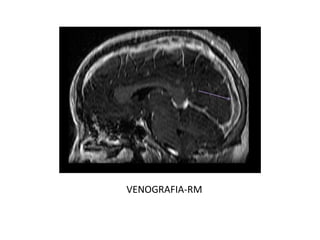

RM

• VENOGRAFIA-RM

El protocolo recomendable ante la sospecha de una TVC es

realizar además de las secuencias potenciadas en T1 y T2 en

al menos dos planos, secuencias de venografía-RM para

descartar la ausencia de flujo en los senos venosos

principales. Si persiste la duda diagnóstica se puede

administrar contraste para demostrar el signo del delta vacío.

VENOGRAFIA-RM

RM • VENOGRAFIA-RM El protocolorecomendable ante la sospecha de una TVC es realizar además de las secuencias potenciadas en T1 y T2 en al menos dos planos, secuencias de venografía-RM para descartar la ausencia de flujo en los senos venosos principales. Si persiste la duda diagnóstica se puede administrar contraste para demostrar el signo del delta vacío.